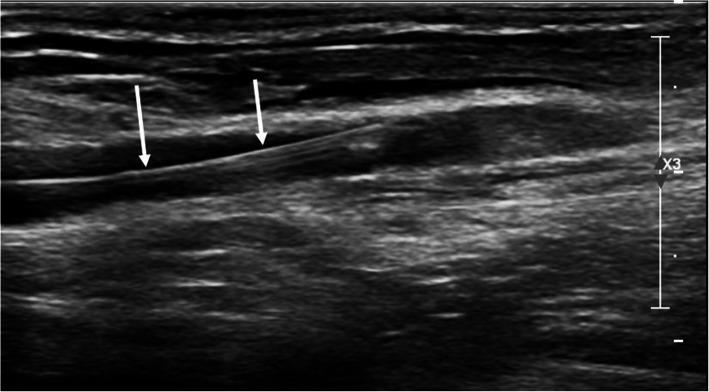

Fig. 2.

Longitudinal ultrasound picture of 19G puncture needle and guidewire (white arrows), which was inserted under live ultrasound guidance

Our results indicate that the consistent use of ultrasound guide for brachial artery access results in a low number of access site complications (Fig. 3). Especially major complications that require surgical intervention appeared at a low rate of 2.7%. Moreover, brachial artery thrombosis resulting in upper extremity ischemia did not occur in our series. We hypothesize that with US-guidance, the brachial artery is punctured at the optimal location in proximity to the bony landmark of the medial humeral condyle away from arterial bifurcations. This leads to an optimal compressibility against the medial humeral condyle after removal of the sheath.